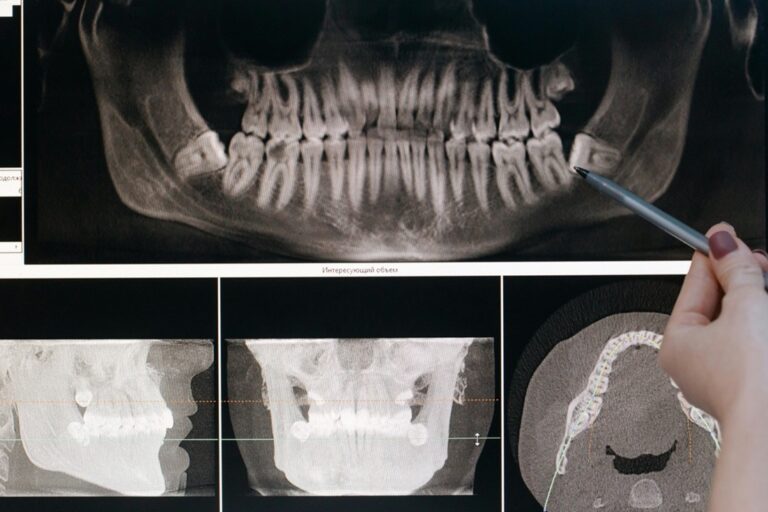

Dental professionals are equipped with modern tools, and they also use digital imaging for accuracy and less trauma removals. Safety protocols are designed to ensure infection control, predictable recovery, and lower risk of complications.